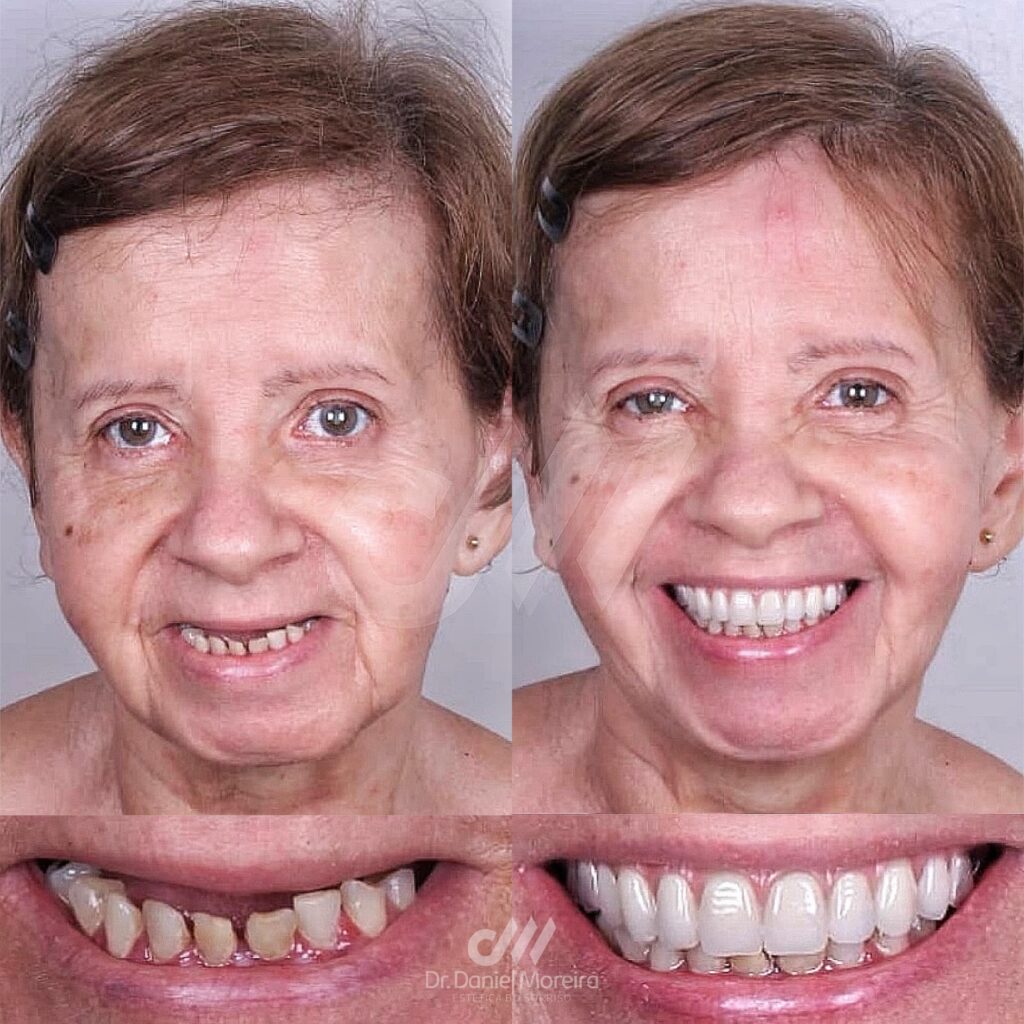

Perder um dente pode afetar muito mais do que apenas a estética do sorriso. Muitas pessoas em Maceió convivem com dificuldades para mastigar, falar e até mesmo com a queda da autoestima por causa da ausência de dentes.

A boa notícia é que o implante dentário em Maceió é hoje uma das soluções mais modernas, seguras e duradouras para recuperar completamente o seu sorriso — devolvendo função, beleza e confiança.

- Aparência natural (parece um dente de verdade)

- Aumento da autoestima

- Segurança ao sorrir e falar

Seu objetivo é entregar não apenas um implante, mas um sorriso harmônico, funcional e natural.

Se você deseja voltar a sorrir com confiança, mastigar melhor e ter mais qualidade de vida, o implante dentário Maceió é uma das melhores escolhas disponíveis atualmente.

Com planejamento adequado e um profissional experiente, o resultado pode transformar completamente seu sorriso — e sua autoestima.